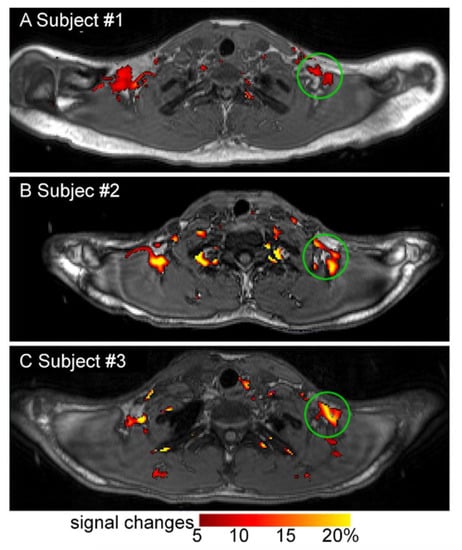

There are several emerging MR-based techniques. Functional MRI may be applied to detect changes in blood flow in activated iBAT in future research although few investigators have used it in BAT research thus far [46]. Blood oxygenation level dependent functional MRI signal increased in iBAT upon cold exposure in one small (n = 3) study with adult humans (Figure 4) [47]. MR thermometry is an emerging technique that measures tissue temperature and may provide an additional measure of iBAT activity [40].

Figure 4.

Change in blood oxygen level dependent MRI signal in human BAT with cold exposure. Change in blood oxygen level dependent MRI signal in supraclavicular BAT with cold exposure (13–16 °C) in healthy human research subjects. Images A, B, and C are representative images of 3 subjects. Image reproduced with permission from reference 47.